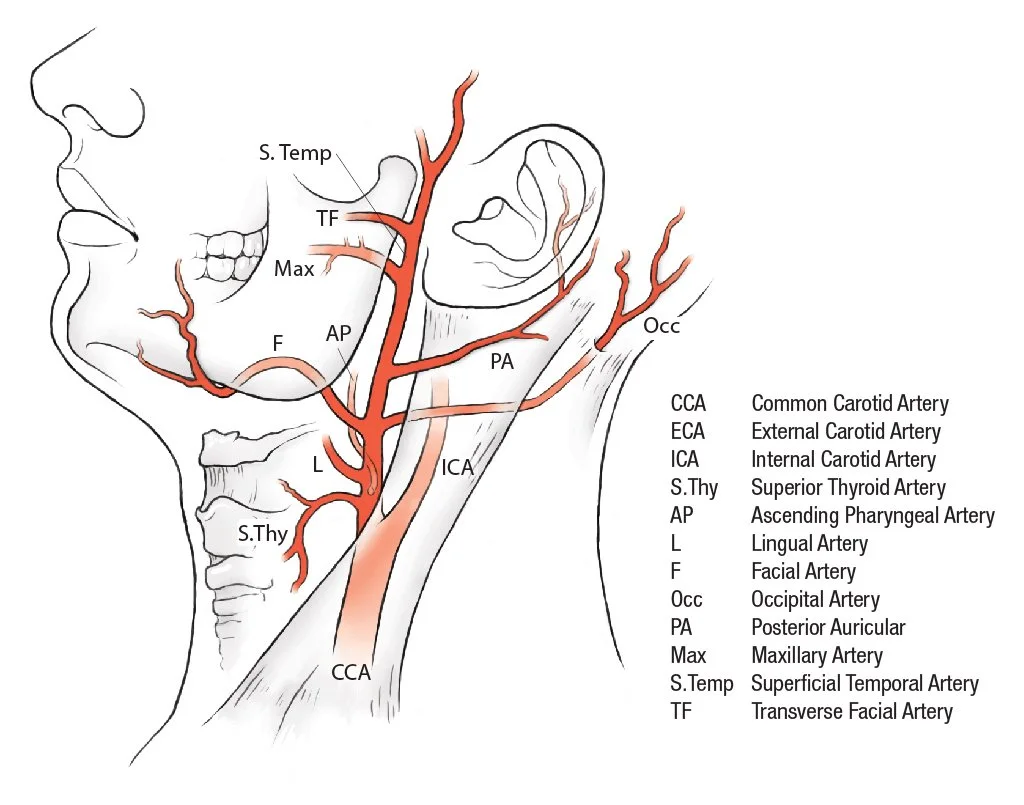

Medical Illustration

All images are works made for hire and are the exclusive property of the client. These are shown as sample purposes of my work only. For licensable work, please see my Illustration Services page.

Medical Illustrator for Precision Graphics, Lachina, and Human Kinetics Publishing (current)

Contract freelancer for many others, some examples of my work below.